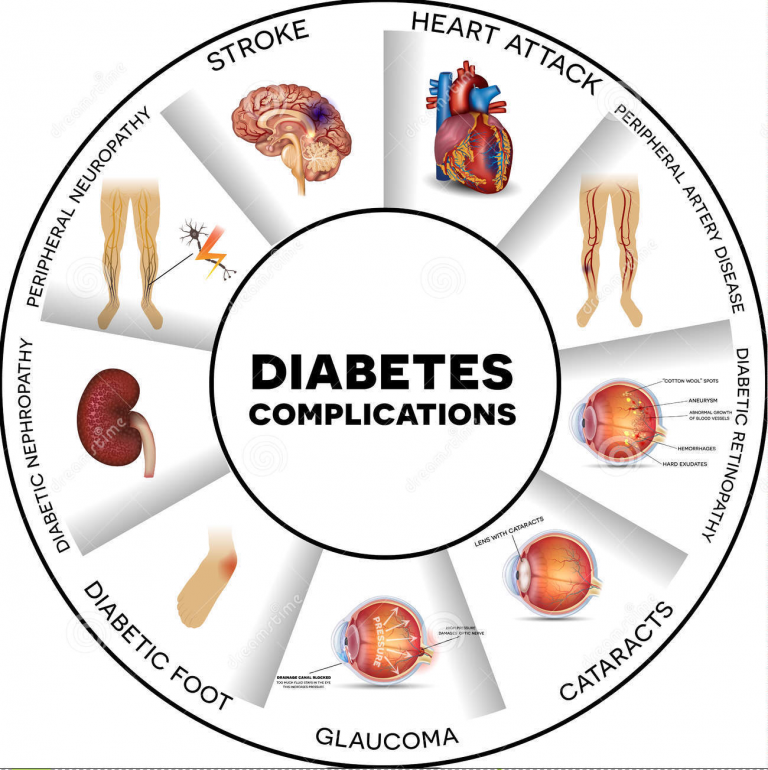

What complications you may develop due to Diabetes?

High blood sugar levels can seriously damage parts of your body, including your feet and your eyes. These are called diabetes complications. But you can take action to prevent or delay many of these side effects of diabetes.

You might hear your healthcare team talk about two types of diabetes complications: serious ones that build up over time called chronic complications and ones that can happen at any time called acute complications.

Chronic Complication

These are long-term problems that can develop gradually and can lead to serious damage if they go unchecked and untreated.

Some people with diabetes develop an eye disease called diabetic retinopathy which can affect their eyesight. If retinopathy is picked up – usually from an eye screening test – it can be treated and sight loss prevented.

Diabetes foot problems are serious and can lead to amputation if untreated. Nerve damage can affect the feeling in your feet and blood sugar can damage the circulation, making it slower for scores and cuts to heal. That’s why it’s important to tell your healthcare professional if you notice any change in how your feet look or feel.

When you have diabetes, high blood sugar for a longer time can damage your blood vessels. This can sometimes lead to heart attacks and strokes.

Diabetes can cause damage to your kidneys over a longer period making it harder to clear extra fluid and waste from your body.

It is known as diabetic nephropathy or kidney disease.

Some people with diabetes may develop nerve damage caused by complications of high blood sugar levels.

Gum disease and other mouth problems:

Related conditions like cancer: